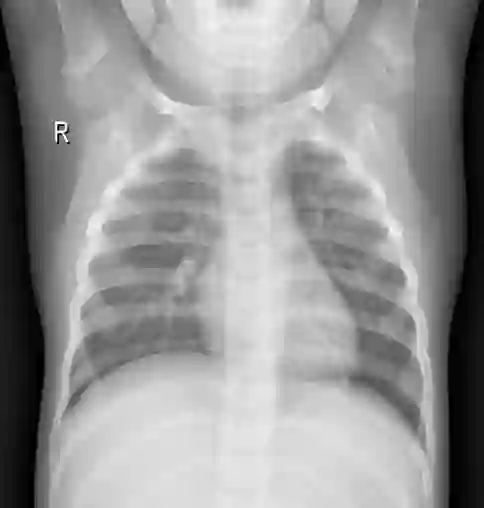

Pneumonia remains a leading cause of morbidity and mortality worldwide. Chest X-ray (CXR) imaging is a fundamental diagnostic tool, but traditional analysis relies on time-intensive expert evaluation. Recently, deep learning has shown immense potential for automating pneumonia detection from CXRs. This paper explores applying neural networks to improve CXR-based pneumonia diagnosis. We developed a novel model fusing Convolution Neural networks (CNN) and Vision Transformer networks via model-level ensembling. Our fusion architecture combines a ResNet34 variant and a Multi-Axis Vision Transformer small model. Both base models are initialized with ImageNet pre-trained weights. The output layers are removed, and features are combined using a flattening layer before final classification. Experiments used the Kaggle pediatric pneumonia dataset containing 1,341 normal and 3,875 pneumonia CXR images. We compared our model against standalone ResNet34, Vision Transformer, and Swin Transformer Tiny baseline models using identical training procedures. Extensive data augmentation, Adam optimization, learning rate warmup, and decay were employed. The fusion model achieved a state-of-the-art accuracy of 94.87%, surpassing the baselines. We also attained excellent sensitivity, specificity, kappa score, and positive predictive value. Confusion matrix analysis confirms fewer misclassifications. The ResNet34 and Vision Transformer combination enables jointly learning robust features from CNNs and Transformer paradigms. This model-level ensemble technique effectively integrates their complementary strengths for enhanced pneumonia classification.